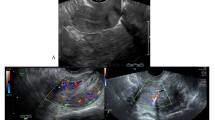

All women presenting with vaginal bleeding underwent transvaginal ultrasound scanning to evaluate the endometrium. The double-wall endometrial thickness was measured in an anterioposterior dimension from one basalis layer to the other. In keeping with departmental guidelines, when endometrial thickness was measured to be less than 5 mm no further investigations were performed as evidence suggests a low probability of cancer below this threshold (Karlsson et al, 1995; Smith-Bindman et al, 1998). For the purpose of the study, we considered all women with endometrial thickness less than 5 mm as negative for endometrial cancer.

Women with endometrial thickness equal to or greater than 5 mm had endometrial sampling performed using an endometrial Pipelle device. Hysteroscopic evaluation of the endometrium with biopsy under a general anaesthetic was performed if Pipelle biopsy was not possible or did not yield sufficient tissue for histological diagnosis. A hysteroscopy was also performed for any woman re-appearing at the clinic for a second time with a recurrent episode of bleeding.